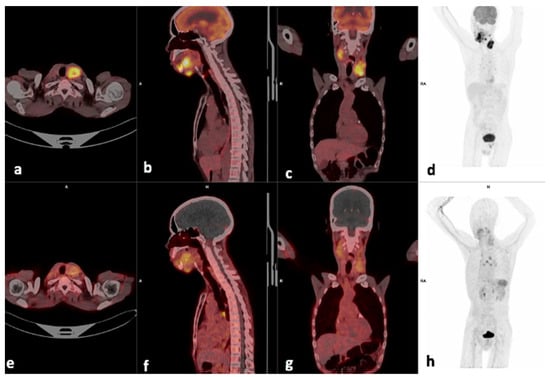

3.3. Visual Analysis